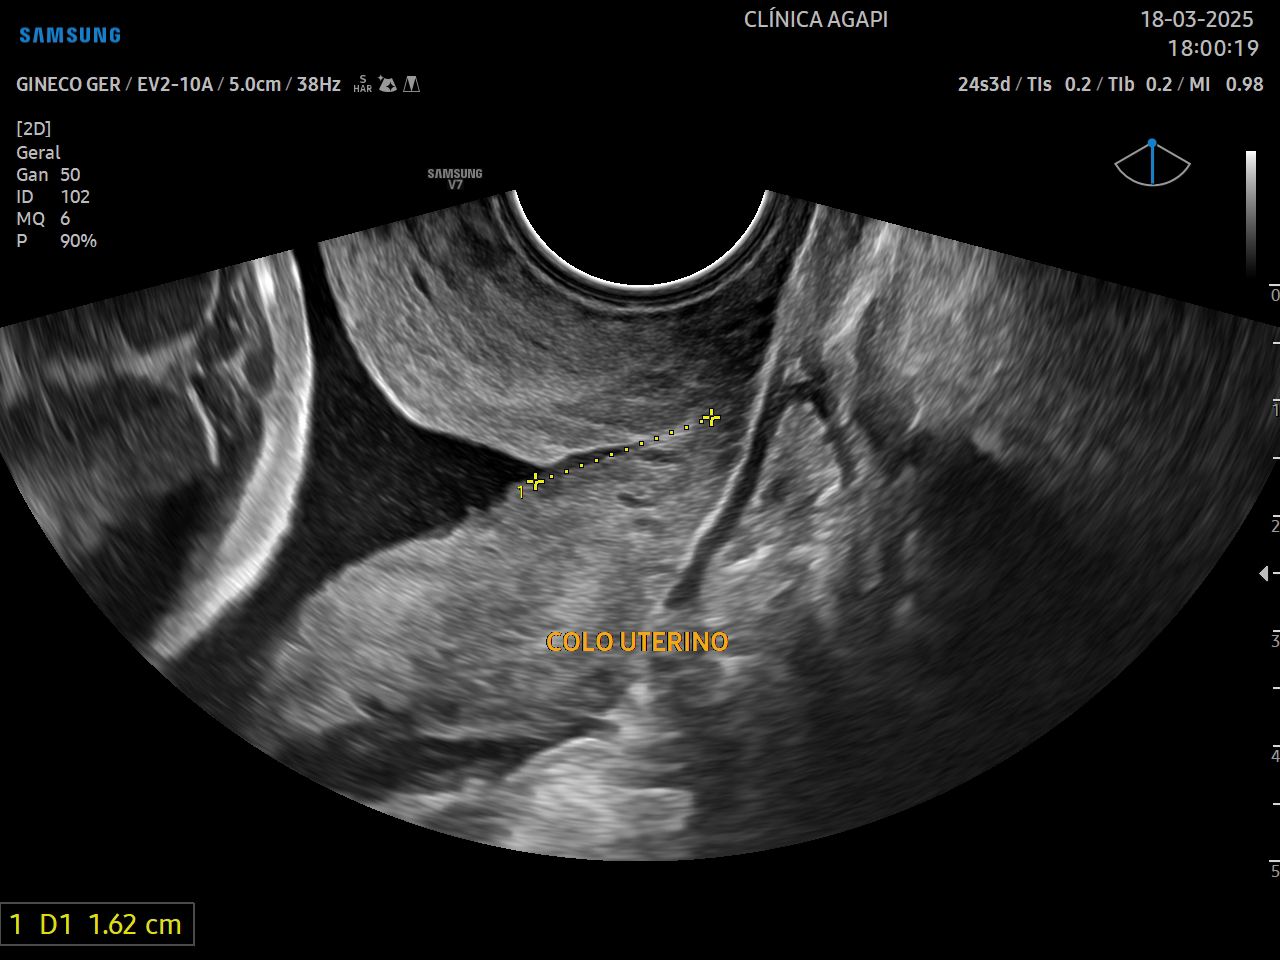

Tem por objetivo identificar pacientes com colo curto, sendo este um dos principais fatores de risco para parto prematuro. O melhor momento para se realizar essa medida é no segundo trimestre.

Através dessa avaliação, pacientes com alto risco podem ser tratadas com medidas preventivas e terapêuticas que visam diminuir o risco do parto prematuro.

Dada a importância deste exame na prática obstétrica, na Agapi, incluímos a medida do colo uterino em TODAS as pacientes que realizam o morfológico de primeiro e/ou segundo trimestre.